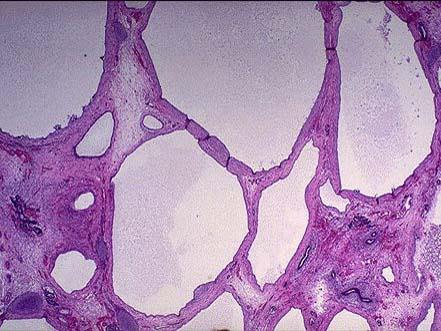

问题 成年男尸,尸检时发现其双侧肾脏肿大,由许多大小不一的囊腔构成,大体如图所示,镜下如图所示,请做出病理诊断 ( )

选项 A.肾细胞癌 B.多囊性肾病 C.肾结核 D.孤立性肾囊肿 E.肾脓肿

答案 B